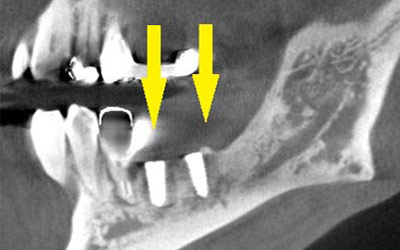

患者様のインプラント治療前のレントゲン写真です。右下顎大臼歯2本の抜歯後のレントゲン写真で、写真の黄色矢印は、歯の周囲の歯槽骨が大きく吸収されてしまっていました。

-

写真のように、CTで見ると、骨吸収の様子が良く分かり、下顎骨の中を通る神経近くまで骨がありませんでした。

さらに、CTで、別な方向から見ると、黄色矢印のように骨が吸収されていて、緑色矢印で示される神経の通る管に迫り、インプラントが埋入できるような骨量はありませんでした。